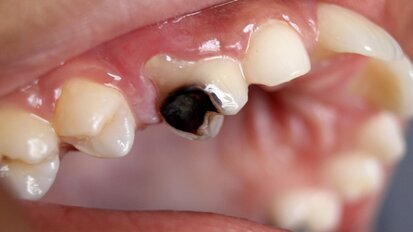

Genetic study suggests a causal link between dental caries and cardiovascular- metabolic factors

UMEÅ, Sweden: Researchers from the Institute of Odontology at Umeå University in Sweden collaborated with the Bristol Dental School in the UK, in the ...